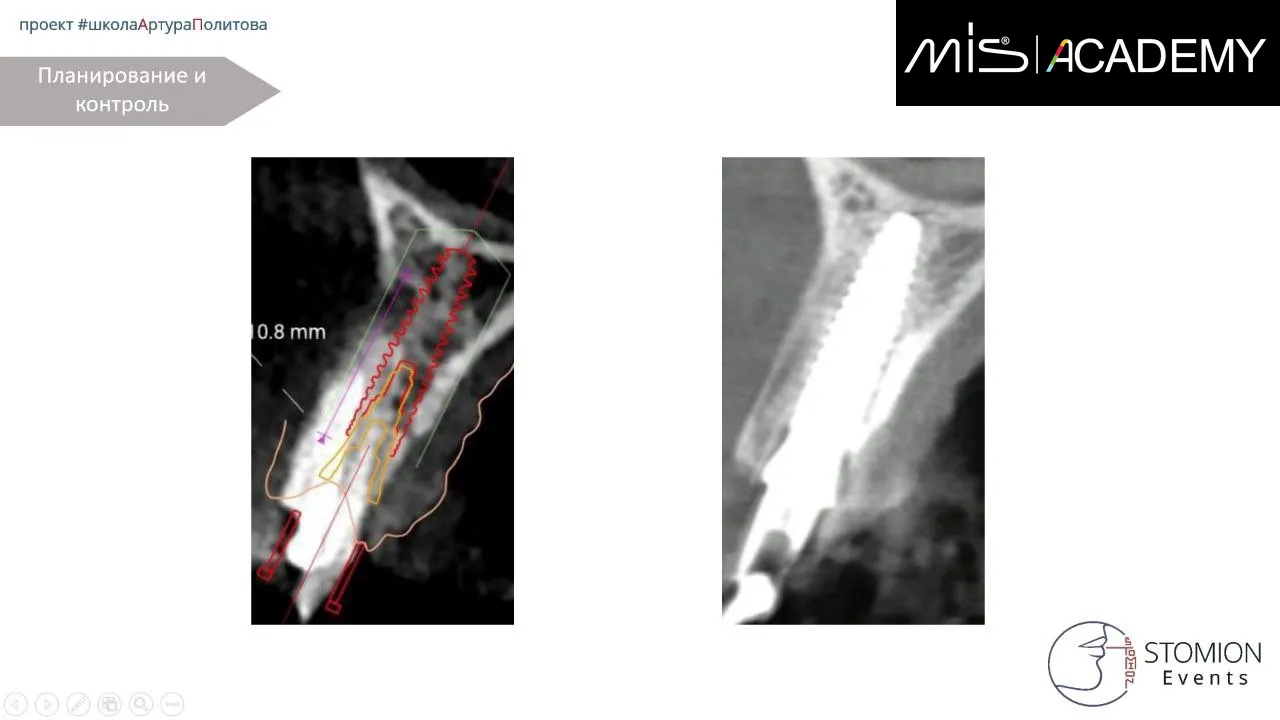

— Удаление 1.2, тип лунки II.

— По НХШ установлен имплантат MIS C1 3,3х13 (для получения торка), забор аутокости с бугра ВЧ, IDR, СТТ вестибулярно, коннект 3мм, немедленная нагрузка временной коронкой, изготовленной до операции, фиксация через позиционер.